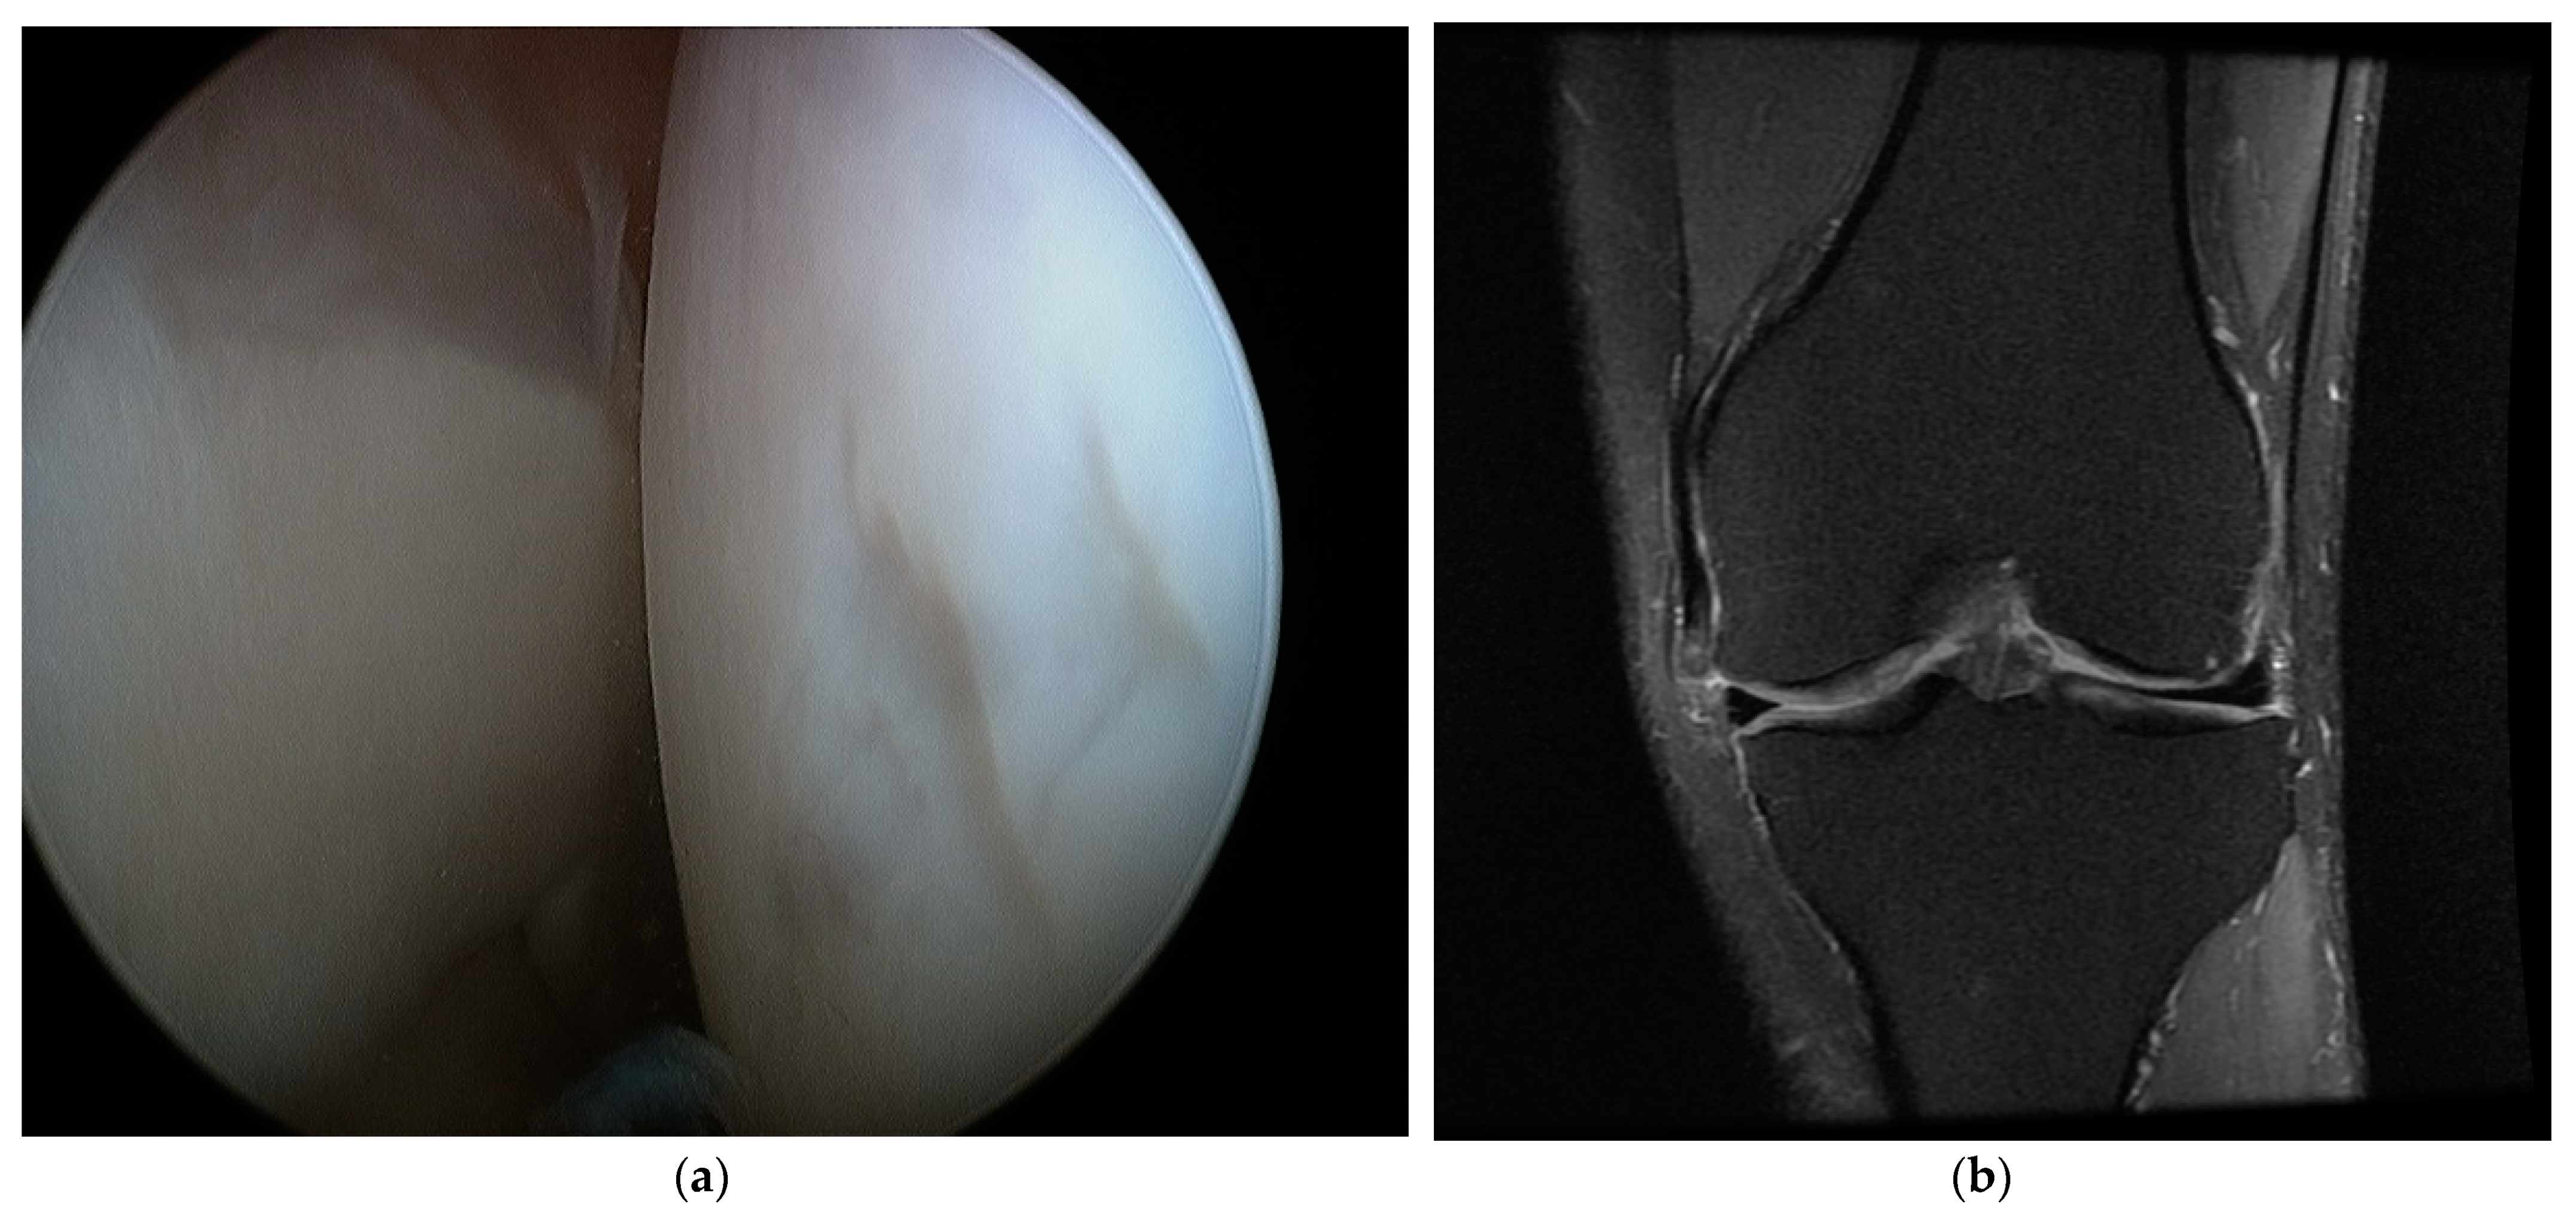

2. Materials and Methods

3. Results

4. Discussion